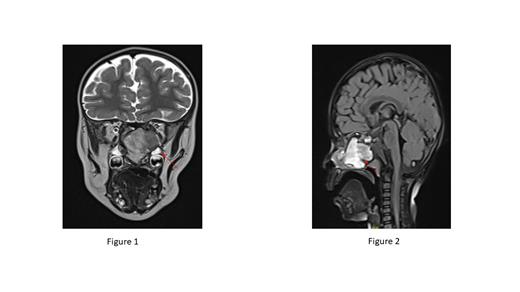

CT and MRI imaging of the orbit revealed an expansible soft tissue mass measuring 2 x 2.5 x 4 cm occupying the right sphenoid sinus, extending to the nasal cavity. The mass had caused erosion of the clivus and the anterior cranial fossa floor, extending to the middle cranial fossa (Figures 1 & 2).

He underwent endoscopic nasal debulking of the left nostril mass, and the pathological examination revealed a cystic mass with a thick capsule and intra-cystic blood clots, consistent with the characteristics of a hemophilic pseudotumor (HP). The fibrous stroma contained hemosiderin-laden macrophages with no evidence of malignancy.